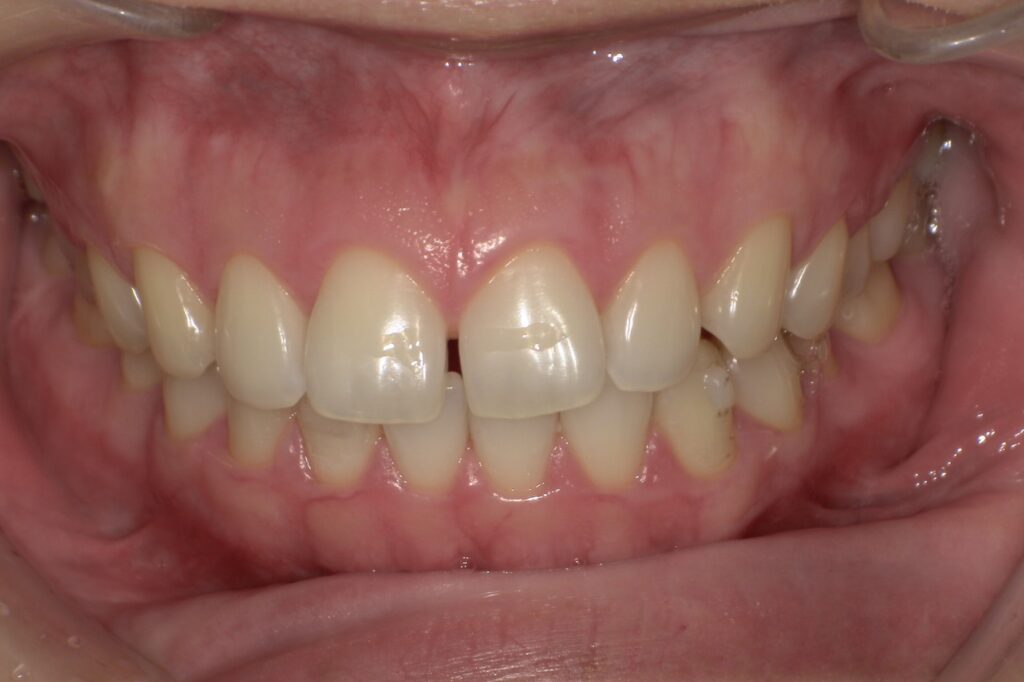

歯が少しだけズレてきた、隙間が開いてきた↓

見た目が気になる、前歯中心の後戻り↓

軽度な後戻り(前歯の傾き・隙間)

1~3mm程度のズレやすき間

例:前歯が少しねじれた/すき間が空いた

中等度の後戻り(複数の歯のズレ)

上下の歯並びが少しガタついてきた